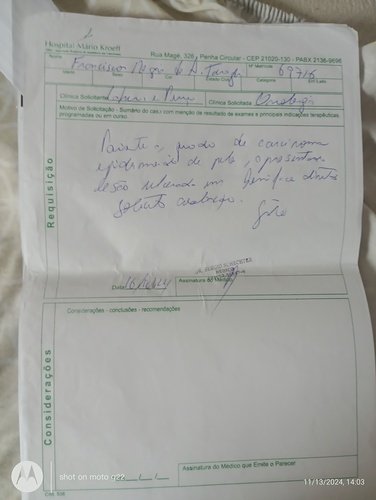

Me chamo Leidiane dos Santos Silva e estou criando essa vaquinha online para ajudar um amigo, pai e muito mais. Ele se chama Francisco Regis de Azevedo Tornaghi. Foi e ainda é uma pessoa que ajuda muitas pessoas e hoje ele está passando por uma fase muito difícil da sua vida. Agora ele está precisando muito da ajuda dos amigos para que ele possa realizar um tratamento de câncer de pele, o qual vem lutando desde o ano passado. Esse ano o câncer voltou e está progredindo de forma muito agressiva. Ele está sendo acompanhado pelo SUS mas o SisReg não dá conta de atender de imediato. Terá que fazer exames muito caros como: análise imunohistoquimico de origem tumoral, tomografia de face, pescoço e tórax. Hoje ele mora em Pedra de Guaratiba e está sendo acompanhado no Hospital MÁRIO KROEFF, na penha, muito longe de casa e fica difícil para a locomoção. Quando começar radioterapia e quimioterapia terá que ir todos os dias. Precisará fazer radioterapia todos os dias e quimioterapia 2 vezes na semana. Para ir de transporte público tem que pegar 4 conduções. Ele não aguenta pois tem 75 anos de idade.Por esse motivo estou aqui fazendo essa vaquinha para que os amigos e familiares possam colaborar com qualquer quantia para ajudar nesse momento muito difícil. Desde já agradeço a todos pela ajuda.